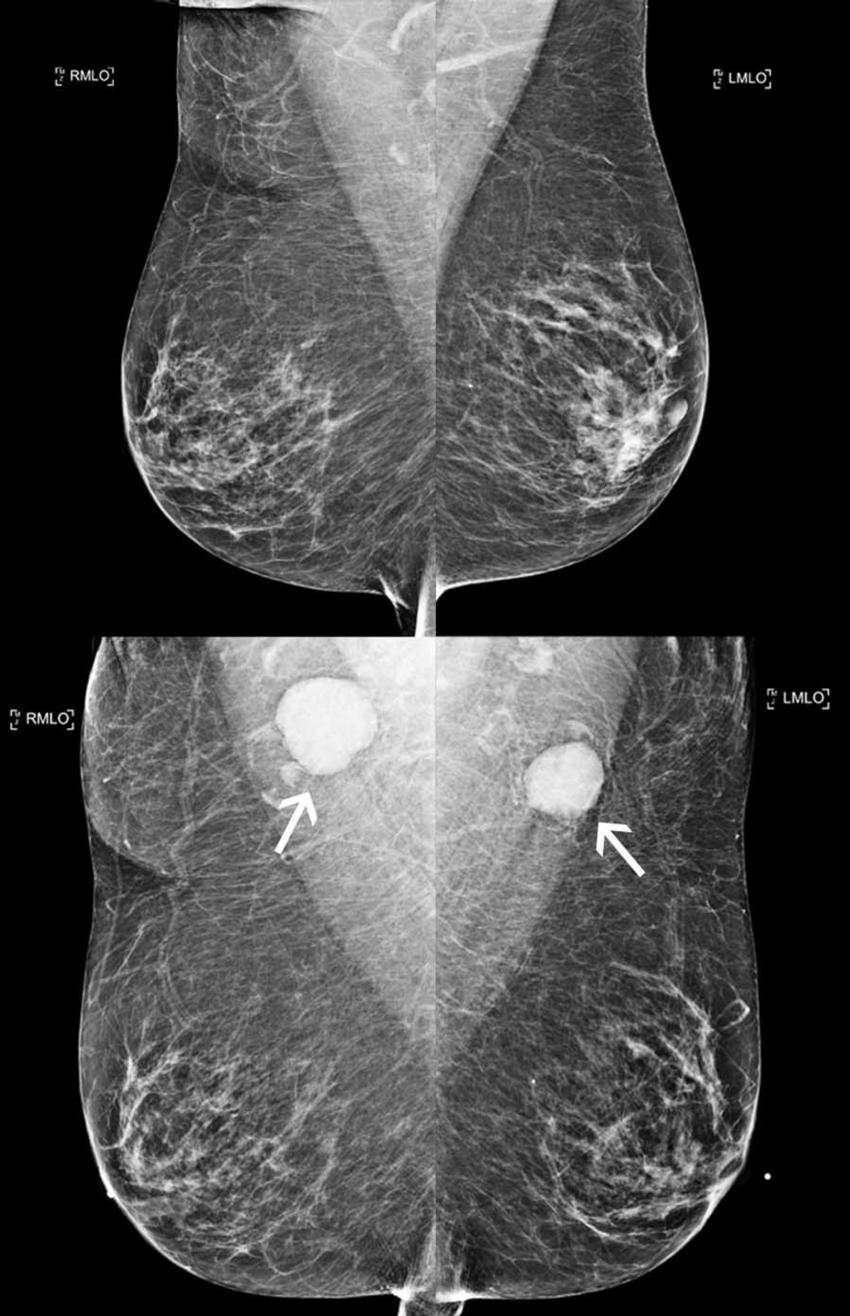

Figure 4. A 78-year-old woman presented for screening mammogram following COVID-19 vaccination. Top row: Bilateral MLO views from comparison mammogram performed one year prior demonstrated morphologically normal appearing lymph nodes. Bottom row: Bilateral mediolateral oblique views following COVID-19 vaccination demonstrated new bilateral axillary lymphadenopathy with enlarged and dense lymph nodes (arrows). Axillary lymph node biopsy yielded follicular lymphoma.

High-res (TIF) version